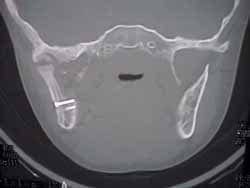

La reconstrucción exitosa, fue determinada mediante los criterios clínicos y radiográficos propuestos por Marx 16 y por August y Kaban (Figuras 6 al 9).(1)

![]() Fig. 6 |

![]() Fig. 7 |

![]() Fig. 8 |

![]() Fig. 9 |

Mediante estos criterios se estableció que 14 pacientes presentaron un procedimiento reconstructivo exitoso (82.35%), 2 (11.76%) fracaso y 1 (5.88%) no determinado (Tabla No. 1)